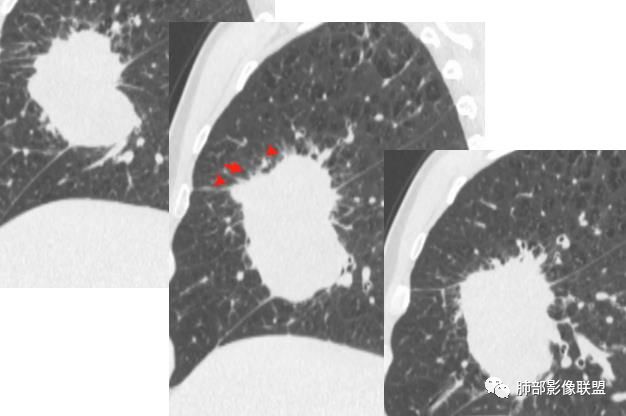

找一下支气管,

上叶支气管没有找到,是没有给还是真的堵了

支气管有阻塞有推挤

中叶支气管还再,推移加堵塞,但是推移为主,我觉得肯定不是中叶的中央起源

下叶也都在

我现在想知道上叶支气管是全部堵了还是没有给都图片。如是没有堵塞,就是外向内的腺癌或间叶来源,如果上叶堵了,就不一样

因为中叶和下叶支气管没有堵塞为主,是外向内的迹象,现在我就是上叶图片的问题

尖,一个是中叶,一个是后叶背段

我也是看到支气管似乎没有堵塞,除外鳞癌

图片还不够全

外侧段是推移为主